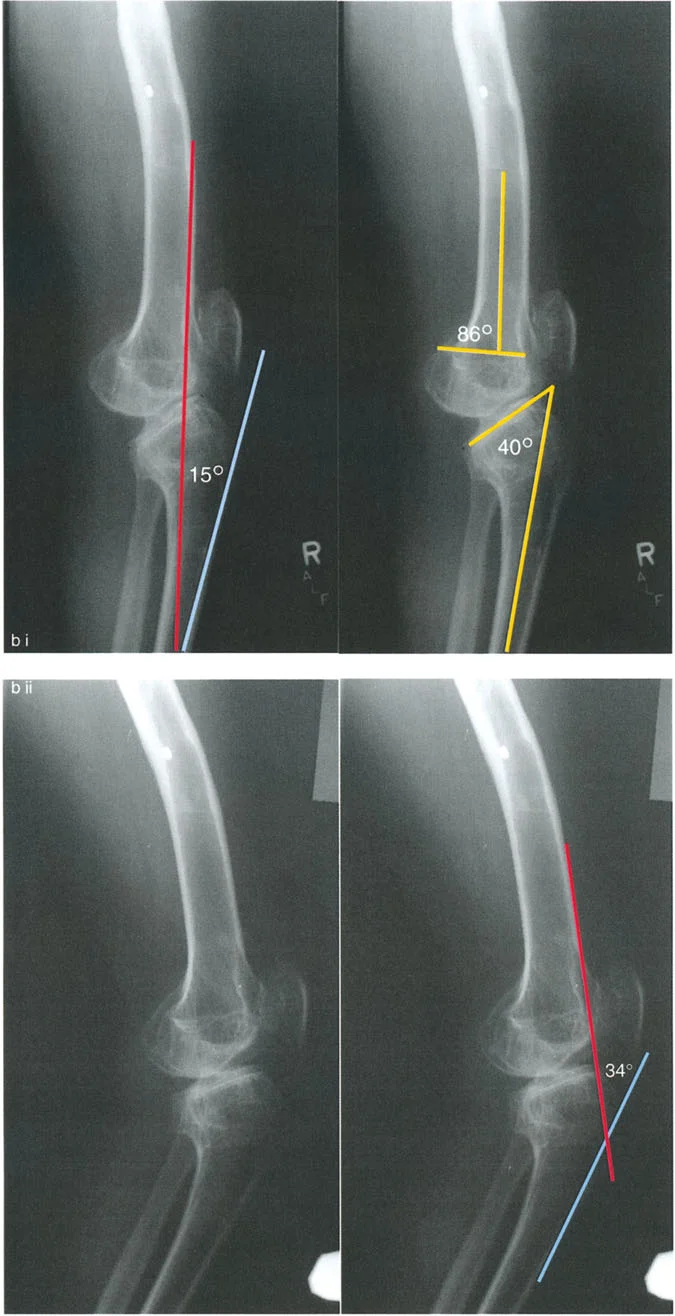

تُعد الأشعة التصويرية ضرورية لتأكيد التشخيص وتحديد مدى الضرر وموقع التشوهات العظمية بدقة:

- الأشعة السينية (X-rays):

- الأشعة الأمامية الخلفية (AP View) والجانبية (Lateral View): تُظهر حالة العظام، تآكل الغضروف (يُلاحظ كضيق في المسافة المفصلية)، وجود نتوءات عظمية (Osteophytes)، وأي تشوهات عظمية واضحة.

- الأشعة السينية الطويلة للطرف السفلي بالكامل أثناء الوقوف (Standing Long-Leg AP View): تُعد هذه الأشعة حاسمة لتقييم المحاذاة الميكانيكية للطرف السفلي بأكمله. تُظهر بدقة درجة الانحراف الأفحج (Varus) أو الأروح (Valgus) وتساعد في تحديد مركز دوران التشوه (CORA).

- الأشعة الجانبية الطويلة للطرف السفلي بالكامل أثناء الوقوف في أقصى بسط (Standing Long-Leg Lateral View in Maximum Extension): تُستخدم لتقييم تحدد حركة الركبة (FFD) والركبة الارتدادية (Recurvatum)، وتحديد ما إذا كان التشوه عظميًا أو ناتجًا عن تقلص في الأنسجة الرخوة.

تصحيح تحدد حركة الركبة (Flexion Deformity - FFD)

تحدُّد حركة الركبة هو عدم القدرة على مد الركبة بالكامل. يمكن أن يكون سببه عظميًا أو ناتجًا عن تقلص في الأنسجة الرخوة.

- التشخيص الدقيق: يجب تحديد ما إذا كان تحدد الحركة ناتجًا عن تشوه عظمي (تقوس أمامي في الفخذ أو الساق) أو تقلص في الأنسجة الرخوة (الأوتار الخلفية، محفظة المفصل).

تصحيح الركبة الارتدادية (Recurvatum Deformity - Hyperextension)

الركبة الارتدادية هي فرط البسط في الركبة. غالبًا ما تكون غير مصحوبة بأعراض في الأشخاص ذوي العضلات السليمة، ولكنها قد تسبب مشاكل في حالات ضعف العضلات أو التشوهات العظمية.

- التشخيص: يجب تحديد ما إذا كانت الارتدادية عظمية (تقوس خلفي في الفخذ أو الساق) أو ناتجة عن رخاوة في الأنسجة الرخوة أو ضعف عضلي.